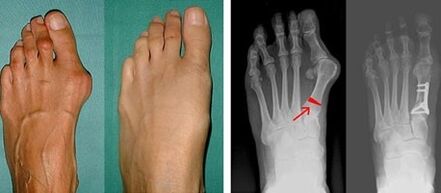

Lors de la première étape de l'identification du valgus du gros et du petit orteil, le médecin procède à un examen visuel. De cette manière, il détermine le stade de développement de la pathologie. Afin d'identifier les changements détaillés dans les articulations, des radiographies et une plantographie sont prescrites.

Si l'examen visuel et les radiographies ne donnent aucun résultat, le patient est alors référé à une plantographie pour déterminer d'éventuels pieds plats. Cette méthode consiste à prendre des empreintes de pieds, sur la base desquelles des chaussures ou des semelles intérieures aux propriétés orthopédiques sont fabriquées pour le patient. Le patient se voit alors prescrire une podométrie. Cette méthode utilise une analyse informatique pour déterminer la pression du poids d'une personne sur les pieds. Les résultats des diagnostics avancés constituent la base du choix d'une méthode de traitement pour la courbure du premier et du deuxième orteil.